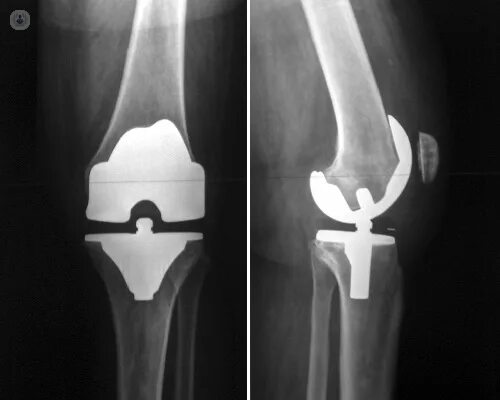

После тотального эндопротезирования коленного сустава